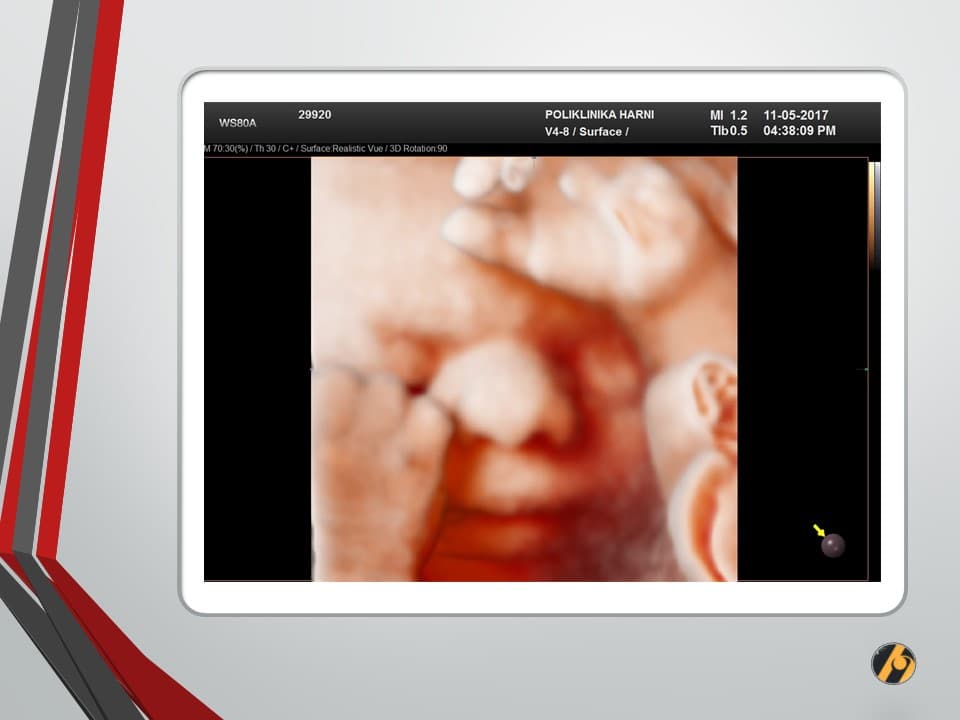

Vaša beba dugačka je oko 39 cm i teška 1,100 – 1,400 g.